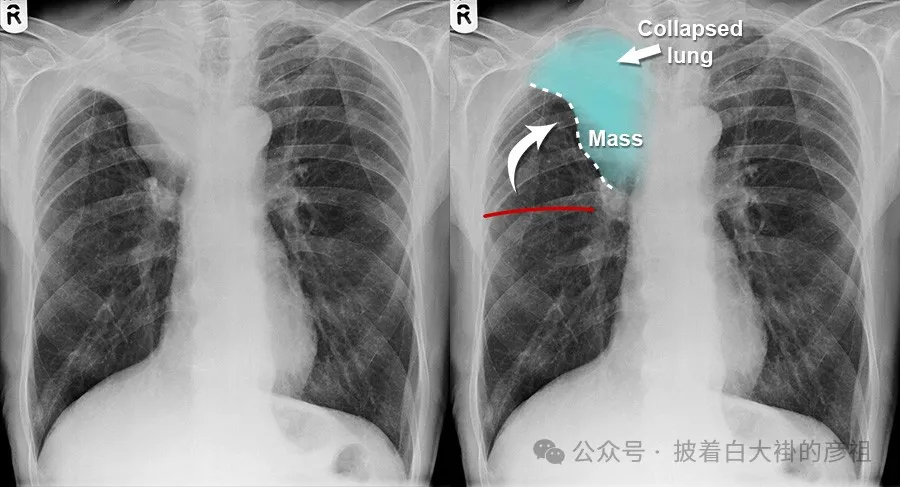

肺不張X片表現